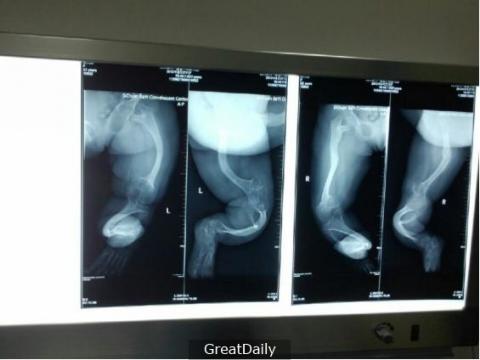

Vợ chồng cô nhanh chóng đưa con đến bệnh viện để kiểm tra. Sau khi chụp X-quang, bác sĩ cho biết xương bàn chân con chị có vấn đề, nó bị uốn cong khá nghiêm trọng. Bác sĩ rất thắc mắc vì sao lại như thế nên đã gặng hỏi người mẹ.

Qua kết quả chụp X-quang cho thấy xương bàn chân của bé có dấu

hiệu bị cong.

Theo bác sĩ phân tích, khi trẻ đang ở độ tuổi học đi, ngoài việc học cách đi, dáng bộ và cử chỉ nó cũng ảnh hưởng nhiều đến cách hình thành bàn chân của trẻ. Khi đi giày rộng, bàn chân trẻ bước đi sẽ không được vững chắc, bị xô dịch trong chiếc dép rộng lớn. Chính vì thế xuất hiện hiện tượng bàn chân bị cong.